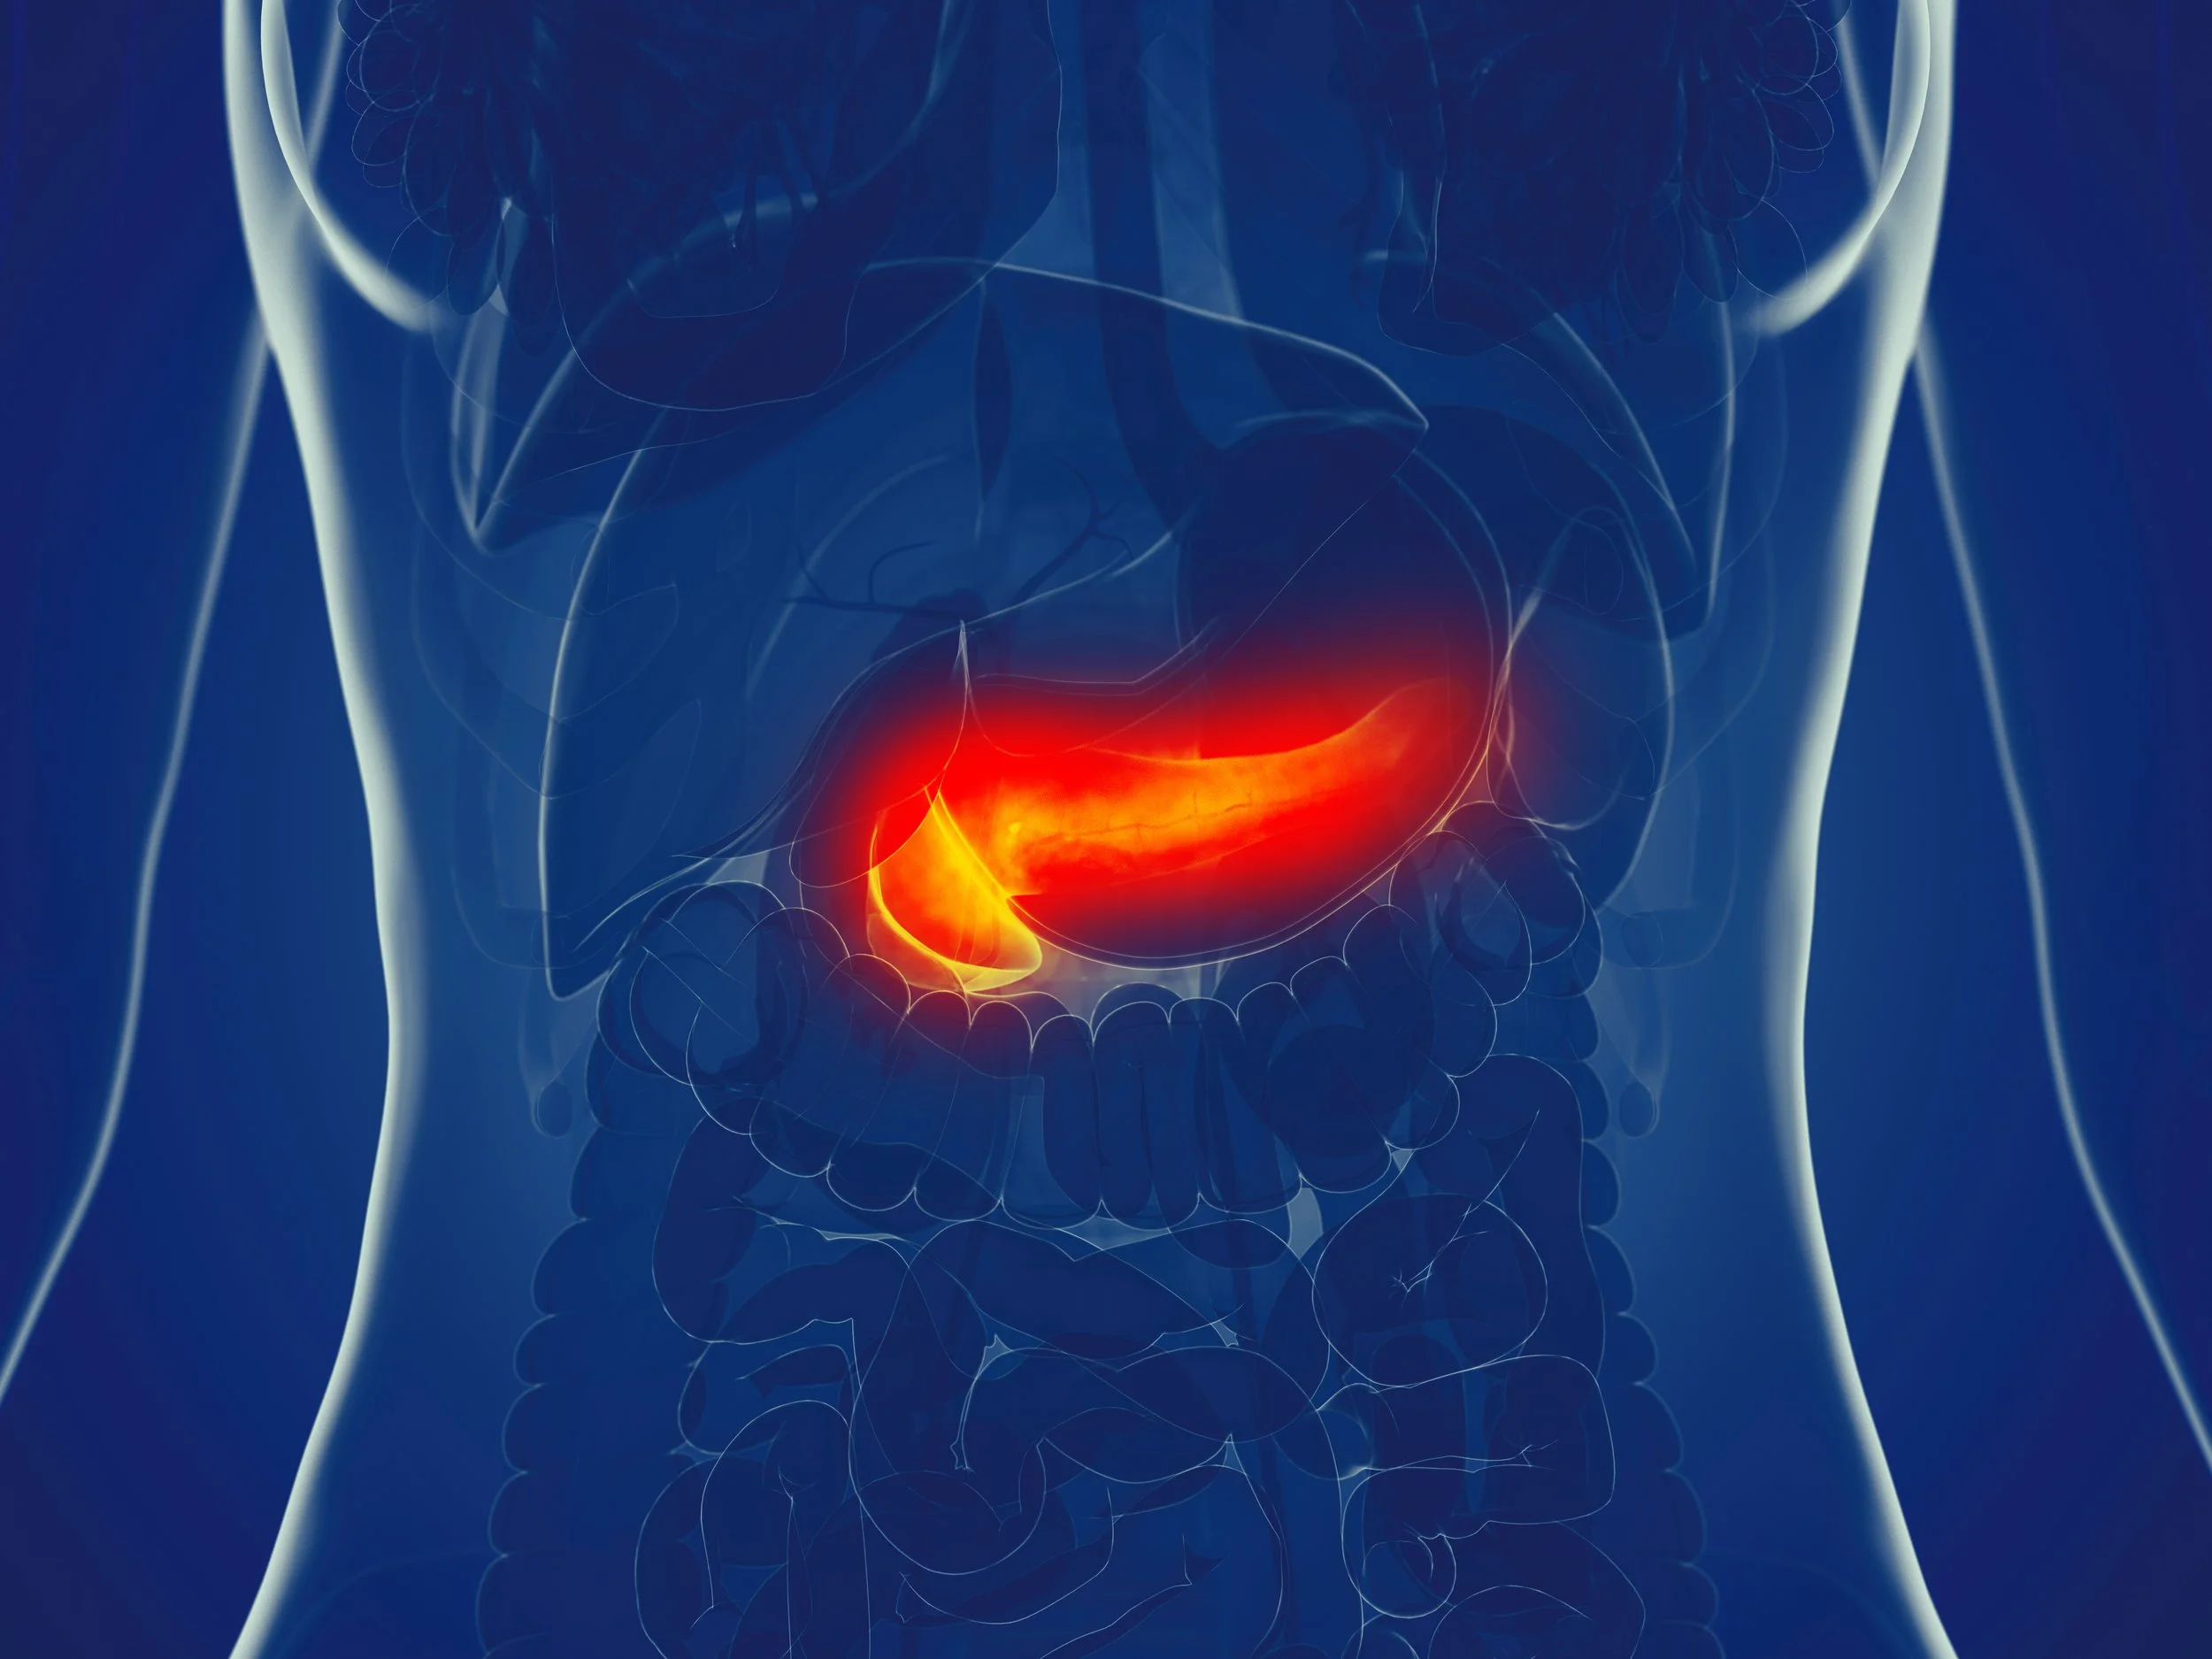

Acute Pancreatitis in 2025

Gastroenterology Dillon Warr Gastroenterology Dillon Warr

Acute pancreatitis: common, painful, and often over-imaged.

Diagnosis usually just needs pain and a lipase 3× ULN—no CT required. The 2024 ACG guidelines emphasize moderate LR resuscitation (not aggressive), early enteral feeding, and early cholecystectomy for gallstone cases. Most cases are mild, but 1 in 5 can worsen fast, so disposition hinges on oral tolerance, vitals, and follow-up reliability.